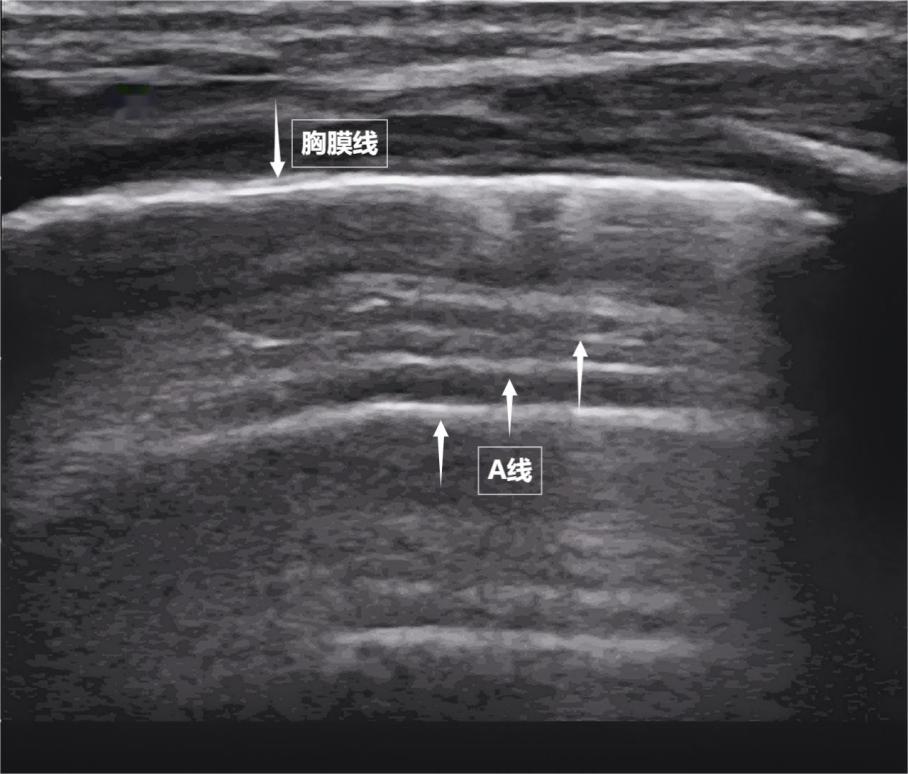

當聲波穿過胸壁肋骨縫隙,首先會遇到緊貼肺表面的光滑薄膜——壁層胸膜和髒層胸膜。兩者緊密相貼,中間沒有多餘的氣體或液體。它們在屏幕上呈現爲一條明亮、光滑的水平線,共同構成了胸膜線。這條線就是肺的“海岸線”。在它的下方,由於肺泡內大量氣體對聲波的強烈反射,會出現一系列與胸膜線平行的、等間距的、重複出現的明亮平行線,像海浪般不斷向屏幕深處延伸,這就是A線(見下圖)。A線是正常含氣肺部的典型標誌。它的存在直接提示肺表面含氣充足,胸膜腔內無異常積液或氣體。

圖爲正常新生兒肺部超聲表現